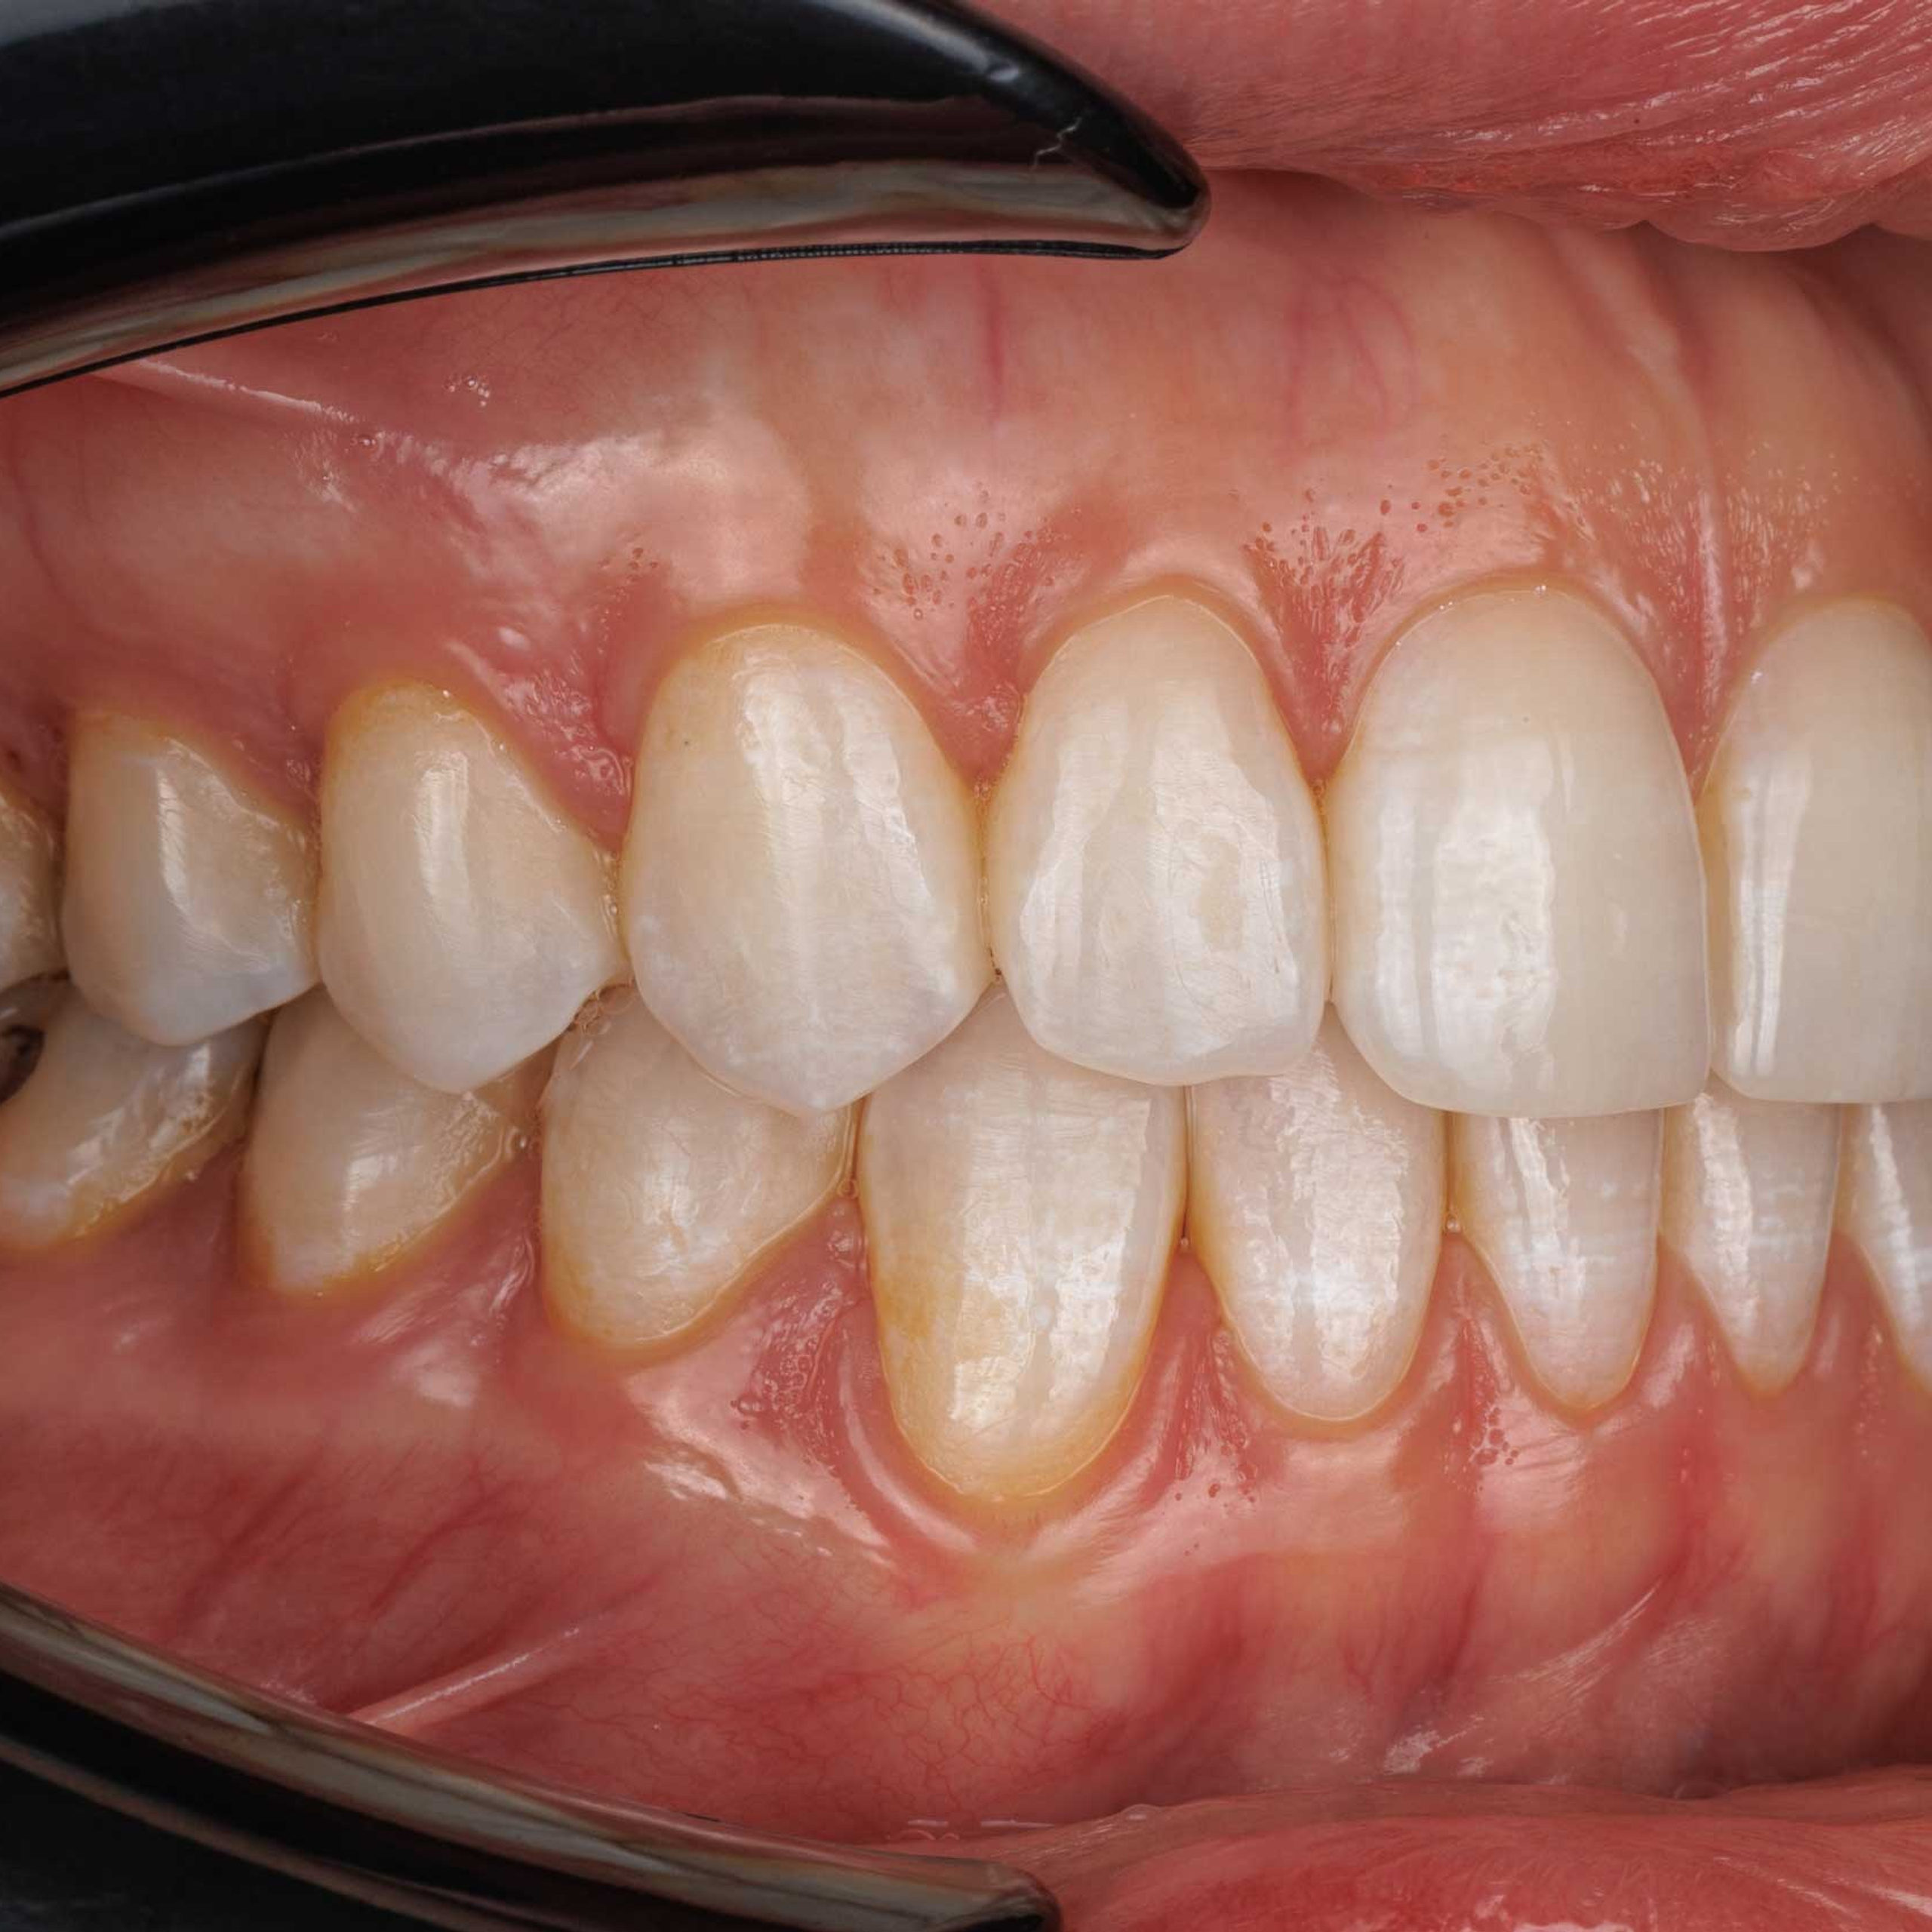

Фотографии учеников до обучения

Фотографии после обучения